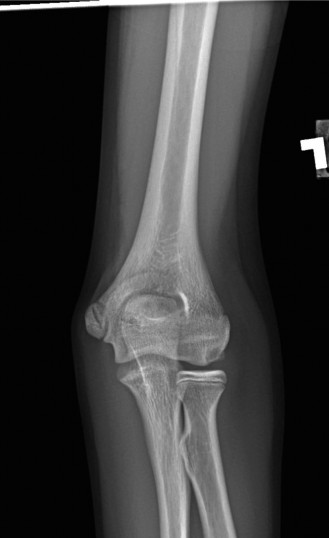

Standard radiographic evaluation of the thrower's elbow must include true anteroposterior (AP), lateral, oblique, and axial (cubital tunnel) views. In this patient, the AP view may appear relatively unremarkable, though subtle hypertrophy of the medial epicondyle or radiocapitellar sclerosis may be noted. The true lateral radiograph is highly informative, often demonstrating the presence of a posterior olecranon osteophyte.

However, the most critical view for diagnosing VEO is the internal rotation oblique view, or a specialized axial view of the olecranon fossa. In our patient's radiographs, we observe a distinct, hypertrophic osteophyte on the posteromedial aspect of the olecranon process. There are also faint radiopacities within the posterior compartment, highly suggestive of intra-articular loose bodies resulting from the fragmentation of these osteophytes.